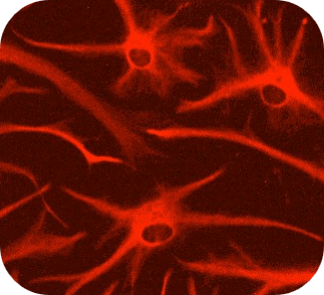

共培養モデル・神経炎症モデル (ミクログリア × アストロサイト × 神経細胞)

ミクログリア x アストロサイト x 神経細胞の3者共培養により、脳内環境を再現し、神経炎症カスケードの可視化や、Ca2+イメージングにて神経活動評価が可能です。